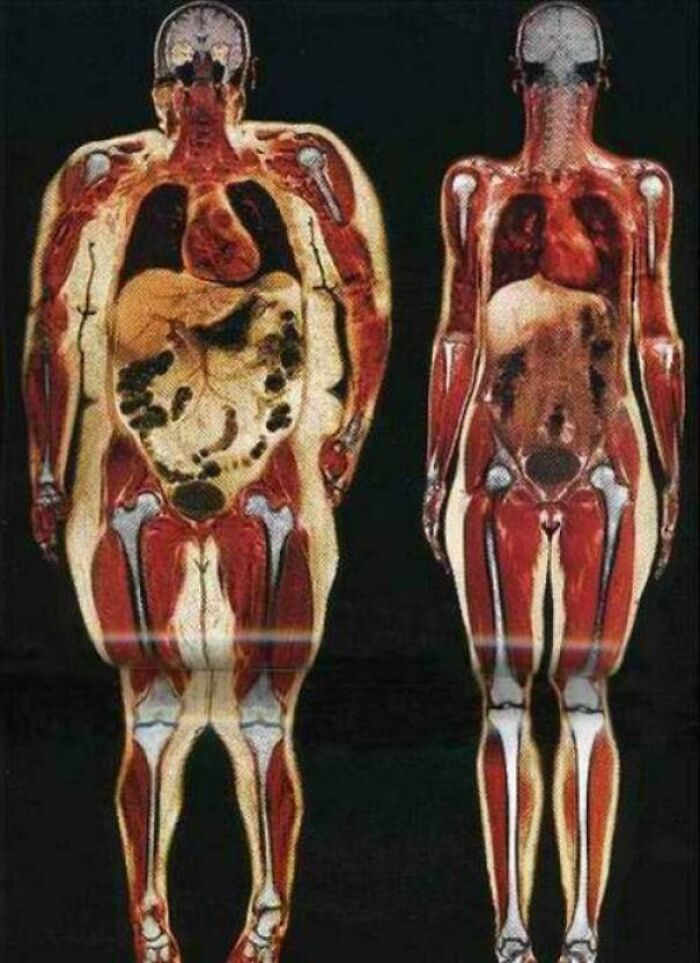

Bodyscan Of Woman At 250 And 125 Pounds

Adler221:

Seeing my MRI scan when I was close to 300, was exactly what I needed to lose weight. Started at 262 and currently 168.